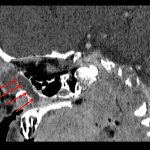

- Peripherally enhancing fluid collection along the left medial canthus with overlying periorbital skin thickening and an ill-defined collection extending inferiorly from the anterior surface of the left globe

- Dilated proximal left nasolacrimal duct which tapers to normal caliber at the distal third

Peripherally enhancing fluid collection along the left medial canthus measuring 2 x 1.5 x 1.8 cm with surrounding inflammatory changes, consistent with dacryocystitis. Ophthalmology consultation is recommended.

Ill-defined collection extending inferiorly from the anterior surface of the left globe could be reactive, although this could represent an additional site of infection/developing abscess. Recommend correlation with exam.